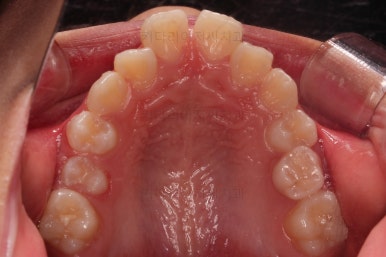

부산소아교정 초진 시 입안의 모습입니다.

윗니가 아랫니보다 많이 앞에 나와있고요.

심지어는 틈새가 벌어지기까지 했습니다.

윗니가 배열 되어있는 U자 형태(그릇 형태)가 아랫니보다 좁은 양상이고요.

이런 앵글씨 2급 부정교합에서는 아랫니가 윗니와 만나기 위해 솟구쳐서 과개교합(아래 앞니가 윗니 뒤쪽으로 깊숙히 올라가 있는 상태)이 나타나기까지 합니다.